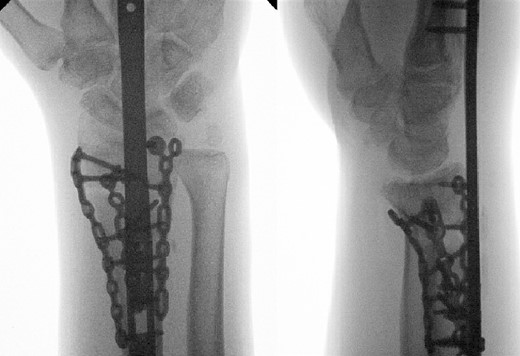

A 43-year-old man presented to the emergency department after falling ~5 ft from a ladder onto his outstretched right hand. He reported immediate pain and inability to bear weight through his right wrist. On physical examination, there was right wrist swelling and limited range of motion (ROM). The skin was intact, and neurovascular exam was normal. The patient had no other injuries and no pertinent medical history. Initial radiographic imaging confirmed a comminuted intra-articular distal radius fracture with dorsal displacement along with an ulnar styloid fracture (Fig. 1). The patient was placed in a sugar-tong splint and followed-up in clinic a week later with surgical treatment planned (Fig. 2).

Preoperative radiological assessment of the patient with postero-anterior (PA) and lateral views of the right wrist.